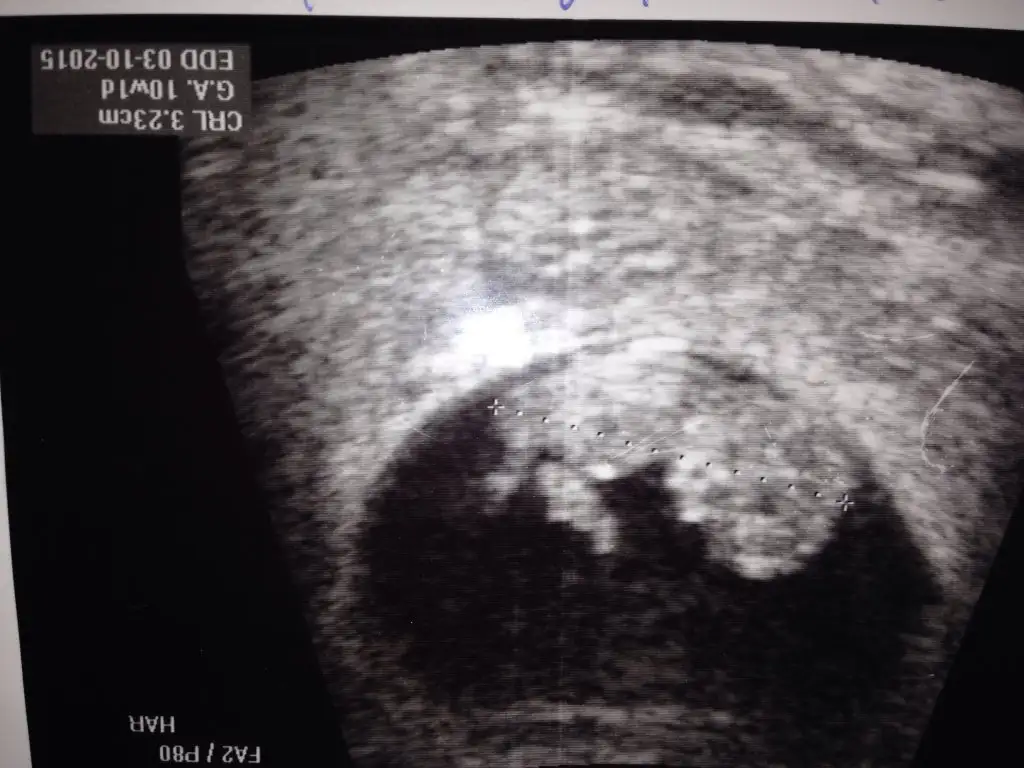

Kızlar Buda 10 haftalık birde buna yorum yapın yarın ultrasona giricem bakalım Hayırlısı

Kizlar bugun ultrasona girdim...radyoloji uzmani bakti..fotolari yukluyorum...o da erkek gibi dedi...once ki dr um kiz gibi...bacakarasi foto atiyorum bi bakabilir misiniz...dr a yarin gosterecem..Eki Görüntüle 1503752

Canım sanki pipiye benzer bir şey var gibi ama hiç seçilmiyor. Daha net olaydı iyiydi..